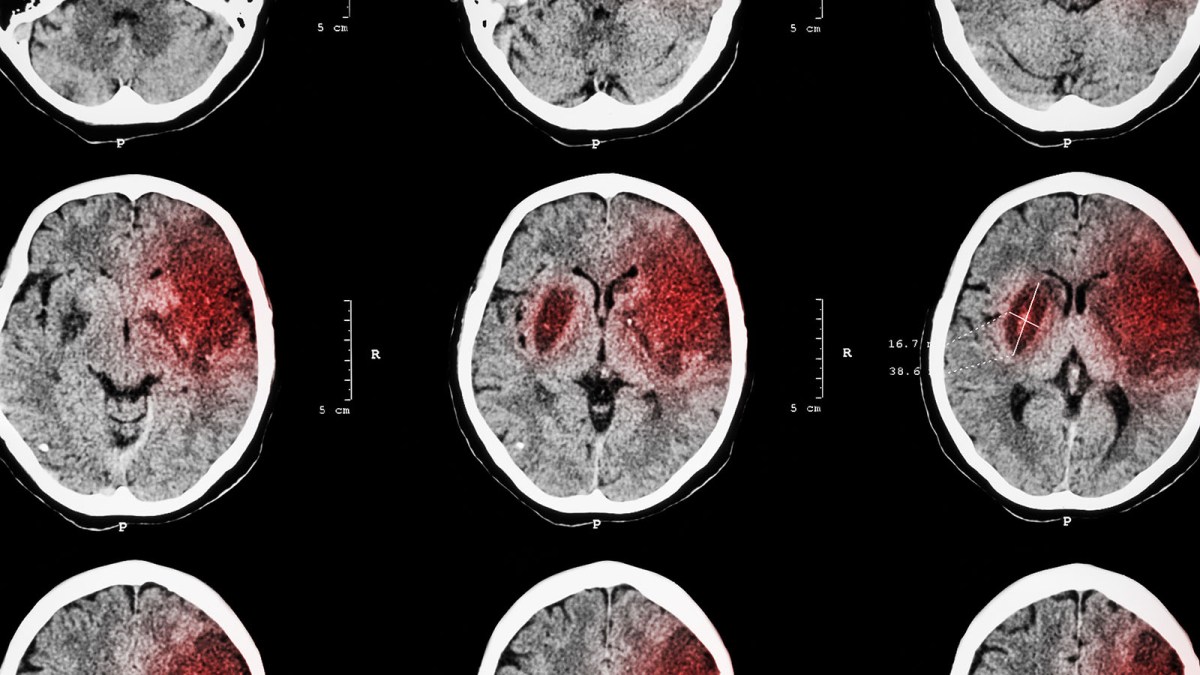

Stroke recovery: An ischemic stroke is caused by a clot choking off blood supply to part of the brain, leading to the death of brain cells in the impacted region.

This can lead to long term complications, including loss of muscle use, difficulty talking and swallowing, and emotional and memory issues.